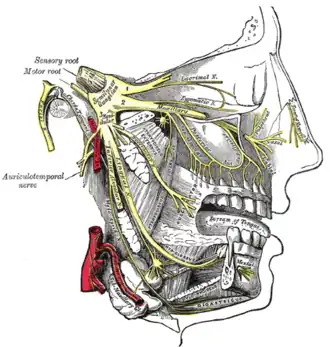

The otic ganglion and its branches. (Pterygoideus internus labeled at bottom right.) | |

Distribution of the maxillary and mandibular nerves, and the submaxillary ganglion.

Distribution of the maxillary and mandibular nerves, and the submaxillary ganglion. -